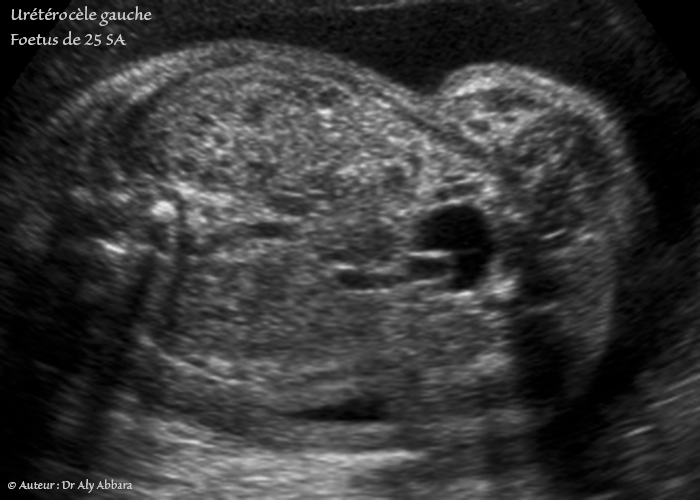

Urétérocèle - Définition, classification, descriptions - Un cas chez un foetus de 25 SA du sexe masculin

Séquence vidéo et auto diaporama (format GIF) d'images échographiques animées montrant une urétérocèle simple gauche occupant partiellement la cavité vésicale. Cette urétérocèle en continuité avec l'uretère gauche dilaté modérément dans sa portion distale.

Il s'agit d'un fœtus du sexe masculin, âgé de 25 SA, et ne présentant pas, par ailleurs, aucune malformation morphologique, en particulier les deux reins sont normaux et les cavités pyéliques non dilatées.

Échographiquement, l'urétérocèle intravésicale prend l'aspect d'une image kystique (une bulle), à paroi fine, implanté sur la paroi postérieure ou postéro-latérale de la vessie. L'urétérocèle peut montrer des fluctuations de son volume en fonction du remplissage de la vessie, du péristaltisme urétéral et de l'évacuation urétérale : elle se gonfle lors l’évacuation de l'uretère (cette évacuation est visible sous forme de jet si on active le Doppler couleur), cela s'explique par le rétrécissement du méat urétéral qui est à l'origine de la formation de cette urétérocèle.

On peut observer également la dilatation la portion pelvienne de l'uretère homolatéral, il s'agit d'une dilatation fusiforme comme dans le cas présenté dans cet article.